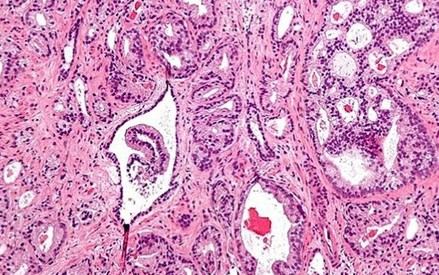

Un estudio del Instituto de Salud Carlos III (ISCIII) revela que la exposición al arsénico aumenta el riesgo de desarrollar cáncer de próstata avanzado en hombres. Analizando muestras de uñas de más de 800 varones, se encontró que aquellos con mayores niveles de arsénico presentan casi el doble de riesgo de sufrir esta enfermedad, especialmente en sus formas más agresivas. Este hallazgo subraya la importancia de controlar la presencia de arsénico en el agua potable y los alimentos para proteger la salud pública y prevenir el cáncer de próstata. La investigación se enmarca en el proyecto MCC-Spain y ha sido publicada en la revista Environmental Research.